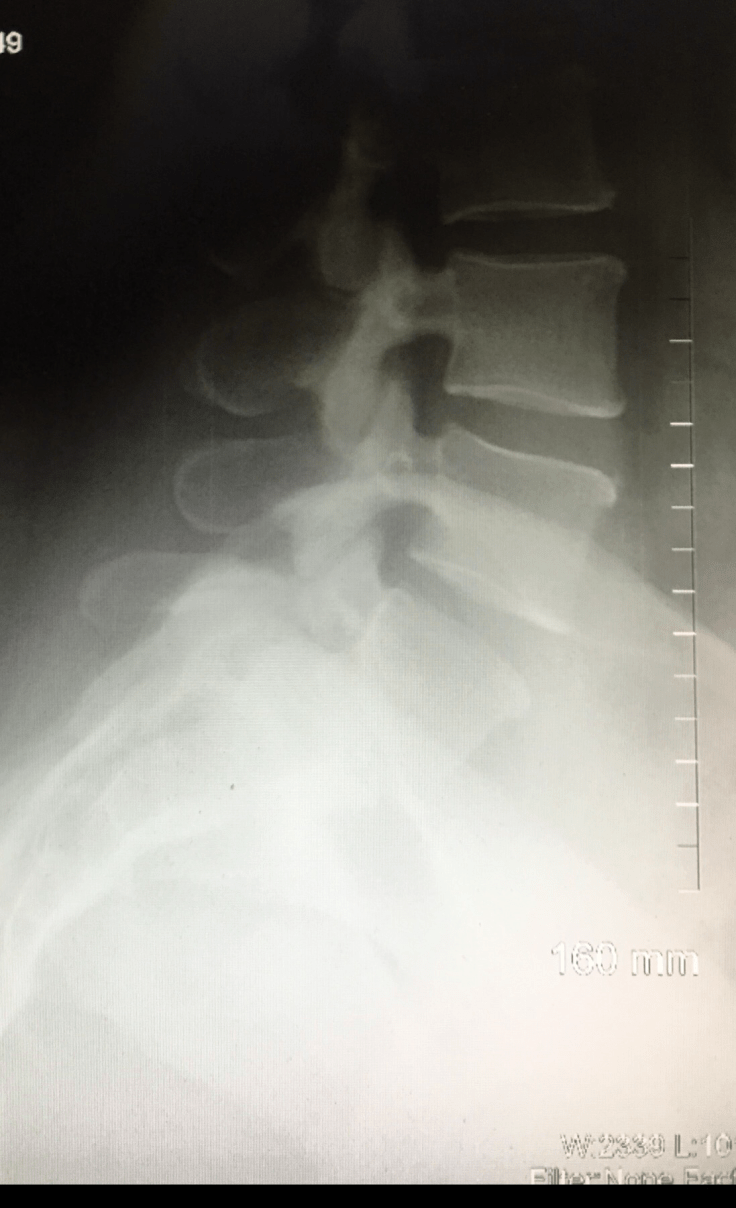

Xray from April 2016 above

Xray from 2012

I found out I had Spondylolithesis and a par fracture in 2016 under the care of my new amazing PCP.

I’m a grade one at least I was in April 2016